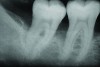

Following active therapy, probing depths of 4 mm or less (Figure 1 and Figure 2) and the absence of bleeding on probing contribute to improved health and stability. Increasing probing depths should alert the therapist to identify etiology and determine whether active periodontal therapy is warranted. The absence of bleeding on probing is a strong predictor of stability, and although the presence of bleeding does not always result in attachment loss, it remains an important parameter to evaluate.14 Bleeding on probing is also an important parameter for assessing implant health during maintenance. Serino et al15 evaluated 27 patients with 19 dental implants over 5 years. Patients were seen every 6 months and they concluded that bleeding on probing was a good predictor for attachment loss and disease progression around the implants (Figure 3).

Fig 1. A deep pocket of 7 mm prior to active periodontal therapy.

Figure 1

Fig 2. Following periodontal regenerative therapy, the tooth with a 3-mm probing depth, which facilitates maintenance.

Figure 2